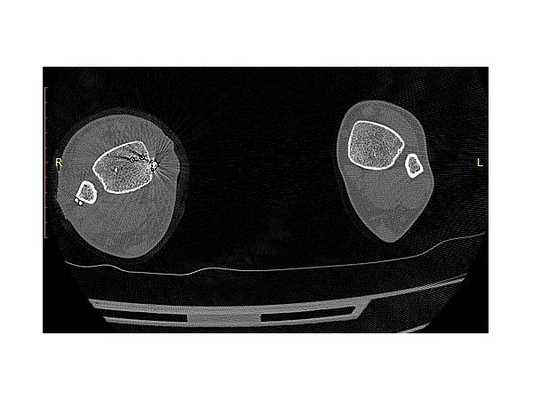

- Компьютерная томография правой голени.

Закрытый оскольчатый перелом внутренней лодыжки правой голени со смещением отломков. Закрытый перелом верхней трети малоберцовой кости правой голени. Повреждение дистального межберцового синдесмоза ( соединения большеберцовой и малоберцовой костей) . Подвывих стопы кнаружи (Maisonneuve-type fracture).